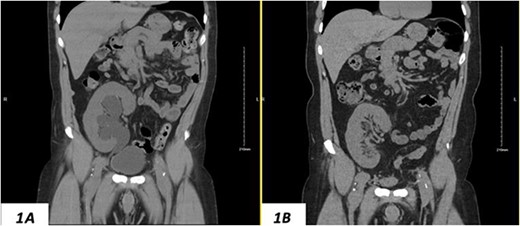

Despite a new onset proteinuria of 50 mg/dl, he continued to have a good functioning graft with a creatinine level of 93 μmol/l corresponding to an estimated glomerular filtration rate (eGFR) of 78 ml/min/1.73 m2. Nonetheless, he had also been noting an inguinal bugle that becomes more prominent as the day progressed, and it regressed at night. Upon further investigations, an ultrasound of the allograft revealed moderate-to-severe hydronephrosis. Further imaging using computed tomography scan (CT) confirmed the presence of upstream moderate hydronephrosis (Figs 1A and2A) along with a reported herniation of the ureter in a right inguinal hernia, resulting in a focal distal ureteric dilatation of 3.5 cm (Fig. 3A).

(A) Hydronephrosis of the allograft ureter on preoperative cross-sectional CT scan; (B) significant improvement of hydronephrosis on the 10-month postoperative image.

The hydronephrosis significantly improved in the 1-year follow-up imaging (Figs 1–3B). The patient continues to enjoy satisfactory graft function with no hernia recurrence. As of July 2023, the patient had further improvement in graft function reflected via a serum creatinine of 76 μmol/l reflecting a eGFR of 99 ml/min/1.73 m2 and 10 mg/dl of proteinuria.